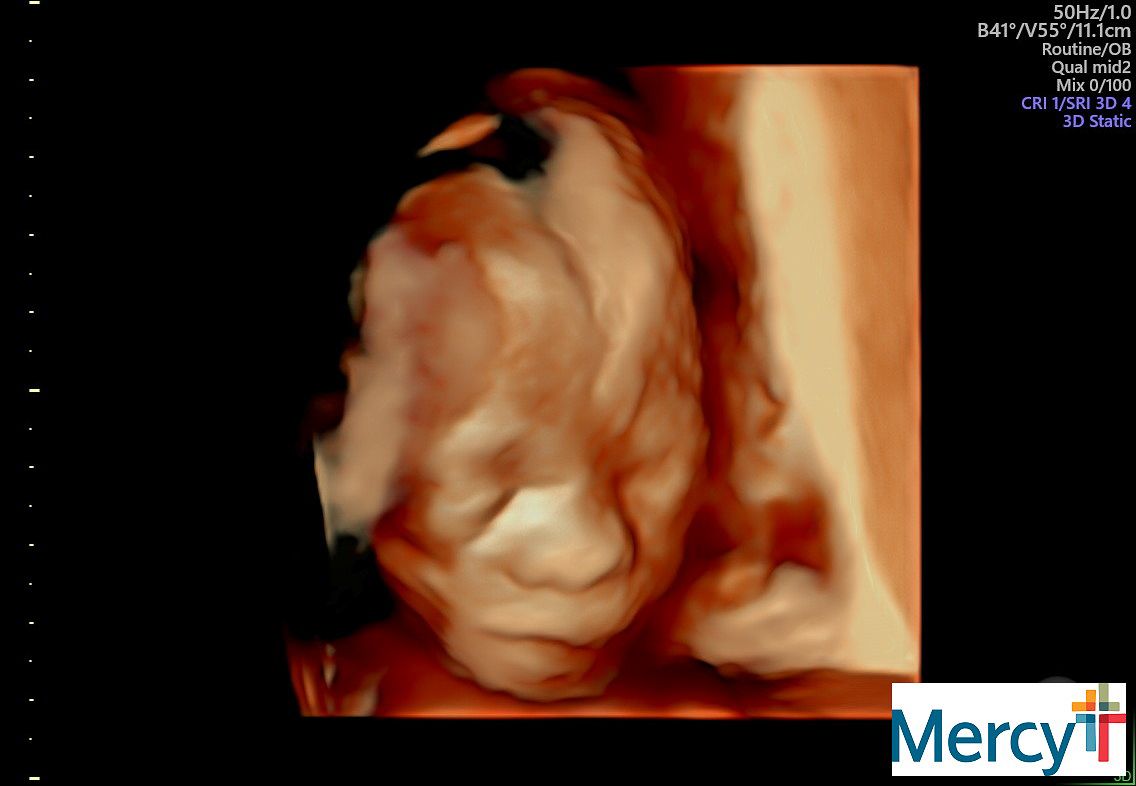

Sydney has her weekly doctor appointment this morning for the baby. Mitzi is grateful she can be there and support. Baby Benson, looking good already!